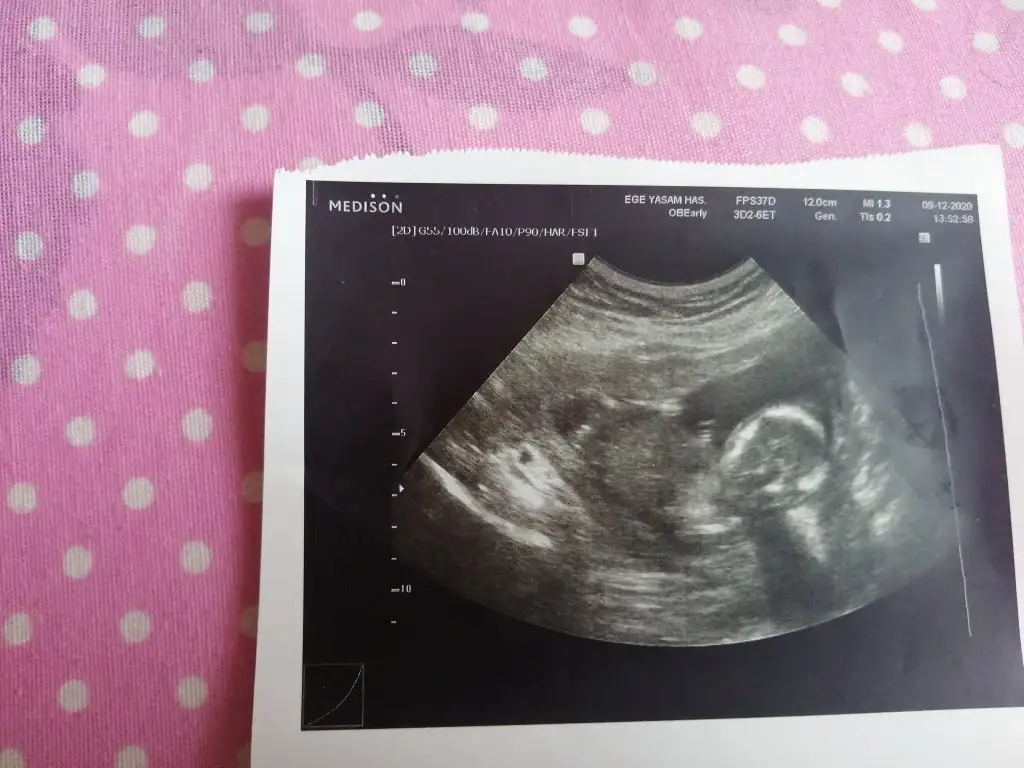

dr soylemeden siz gorun genital nub teorisi ( bebegin cinsiyeti)

Kızlar 12 haftalık yorum yapabilirmisiniz?

Ramzi teorisine göre erkek gözüküyo ama oda kesin çıkmıyo tabi. İlk bebeğinizmi

Erkek ve kız için 11 + 12+ yada 13 hafta usg görüntüsü olmalı açıklamalar asagıda yazıyor 😊 rabbim herkesin gönlüne göre nasip etsin inşallah .. ecmain

[/B]Eki Görüntüle 473828 gordugunuz gibi ust taraftaki simgedende anlasildigi gibi eger cikinti paralel ise kiz

yok 30°lik bir aciyla yukari dogru bakiyorsa %99 oglunuz olacak demektir simdi bi kac ornek resimler daha koyacagim kiziminkide dahil

Eki Görüntüle 473831 simdi burada cikintilara bakin eger bel popo cizgisine paralel ise kiz

yok 30 derecelik bir aciyla yukari bakiyorsa erkek

yabancilarin hepsi biliyor bunu biz neden eksik kalalim gayet bilimsel simdi ellerinde11 12 13 ultrason fotografi olanlar alsin hemen baksin yada koyalim buraya yorumlayalim

iste o nub teorisi kizlar dr buradan yola cikiyor